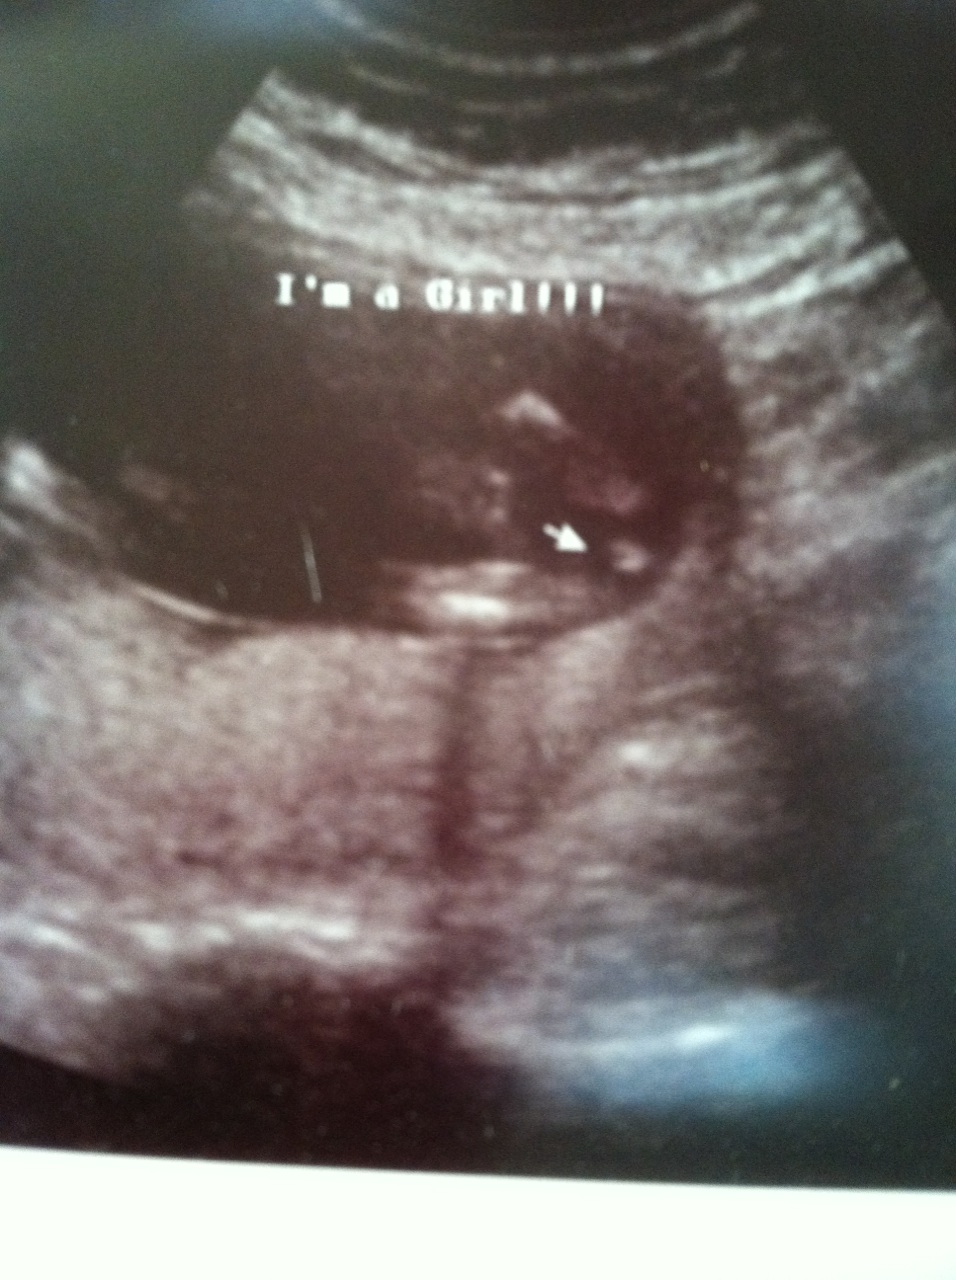

I had an early gender scan done at 15 weeks and was told girl. We did a special reveal at home so during the ultrasound, the tech turned the screen when she looked at the gender and wrote it in an envelope for us. We were thrilled to find out it is a girl, but now that my 20 week ultrasound is approaching next week I am getting a little worried. My shots look pretty girly, but one of the pics looks like it has 4 lines instead of 3 and it doesn't appear to be in line with the legs if that makes sense. Since I didn't see it for myself on the screen, it is bothering me. Anyway, please let me know what you think.![]()

Looks pretty girly, I think the machine just isn't very high res.

Very girly.

Don't worry, that is a girl.

Thanks for all of your responses! You have all helped to ease my mind quite a bit. I know there are many families out there with both genders but for some reason I felt like I would only ever have boys. Now that we have been told girl, I am ready to start celebrating and buying stuff but a small part of me keeps doubting that its true. Thanks again!

girl!!